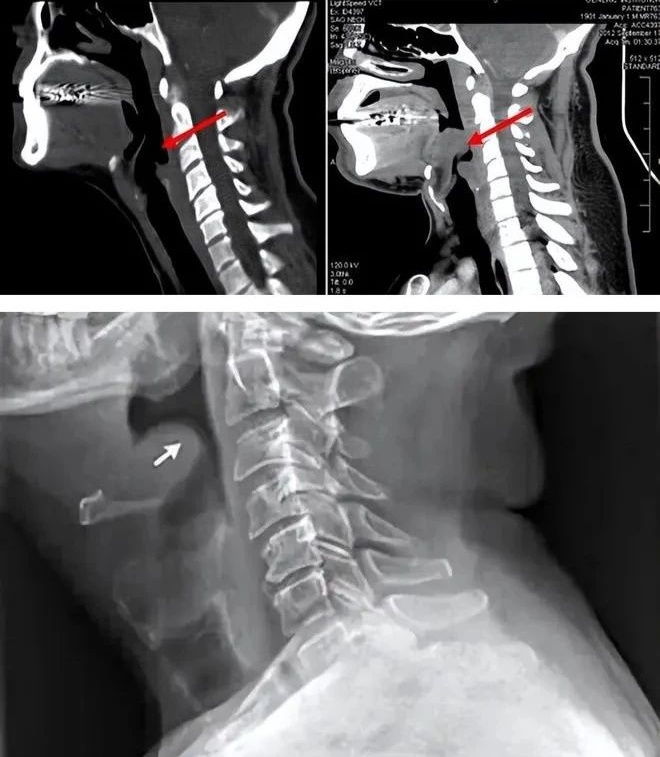

医生结合姑娘之前的种种症状,加之检查时发现她会厌充血肿胀堵塞声门,判断夺命“凶手”是急性会厌炎。急性会厌炎是什么?真那么凶险吗?

会厌是喉部声门上方的一块软骨,位于下气道的入口处,需要借助喉镜才能看见。

2、会厌肿胀,会引起窒息

当会厌发炎,就会出现不同程度的肿胀,严重时甚至会肿成球形,体积超过原来的5-6倍,会厌重量增加,从而遮挡住“喉咙口”,患者就会像被人掐住脖子一样透不过气来。此时如果不及时处理,一旦完全堵塞气道,就会有生命危险了。